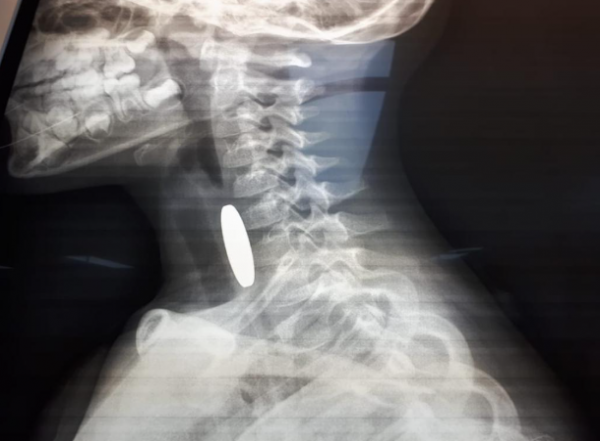

- أنقذت مرتبات دورية نجدة تابعة لشرطة مادبا أثناء الوظيفة الرسمية حياة طفل يبلغ من العمر ثلاثة أعوام ونصف، بعد أن تعرض لحادثة اختناق إثر ابتلاع عملة معدنية في منطقة لواء ذيبان.

وفي التفاصيل، قال والد الطفل محمد الجديعات لإذاعة الأمن العام، إنه وبعد أن لاحظ أن طفله يجد صعوبة بالتنفس قام بشكل فوري بإسعافه باتجاه مستشفى الأميرة سلمى الحكومي، حيث صادف وجود دورية نجدة على مقربة من منزله وعلى الفور استنجد بهم، ليقوم أفراد الدورية بتقديم الإسعافات الأولية اللازمة باحترافية لمثل هذه الحالات بعد أن ابلغهم أنه قد ابتلع قطعه معدنية .

من جانبه قال الوكيل علاء السلايطة، أحد أفراد الدورية: "أثناء وجودنا في المنطقة استنجد بنا والد الطفل وهو يحمل ابنه، فقمنا مباشرة بتقديم الإسعافات الأولية المخصصة للأطفال دون سن الخامسة، وفقاً للتدريبات والدورات التي نتلقاها من مديرية الأمن العام للتعامل مع مثل هذه الحالات حتى بدأت حالته الصحية بالاستقرار واستكمال عملية إسعافه باتجاه المستشفى بواسطة المحطة الأمنية بعد أن تم التنسيق مع غرفة العمليات والسيطرة.